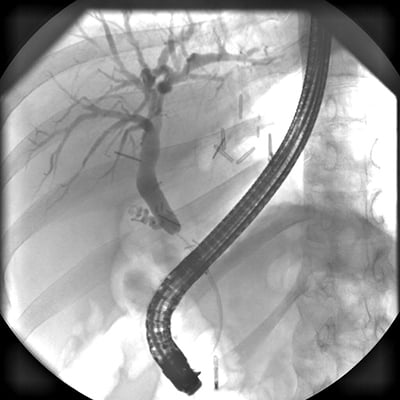

This module will help you perform ERCP exams, as well as standard C-arm procedures and surgical C-arm procedures. Equipment and supplies are discussed, as well as patient preparation, positioning techniques, and technical settings. Personal and equipment protection are covered, as are major anatomical structures seen in these examinations.